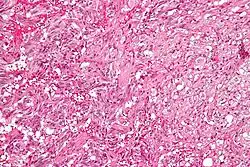

| Micrograph of a gangliocytic paraganglioma. H&E stain. | |

A gangliocytic paraganglioma is a rare tumour that is typically found in the duodenum and consists of three components: (1) ganglion cells, (2) epithelioid cells (paraganglioma-like) and, (3) spindle cells (schwannoma-like).[1]

GP consist of three components (1) ganglion cells, (2) epithelioid cells (neuroendocrine-like), and (3) spindle cells (schwannoma-like). The microscopic differential diagnosis includes poorly differentiated carcinoma, neuroendocrine tumour and paraganglioma.[1]